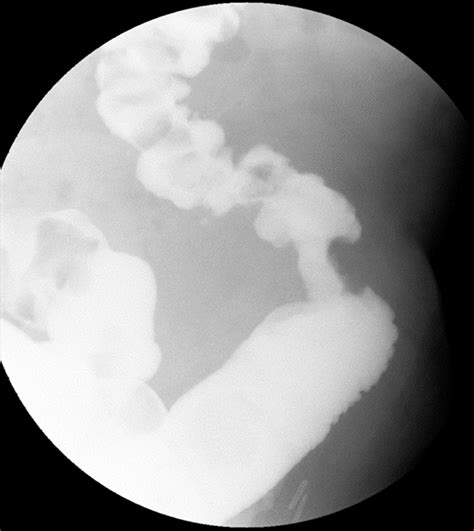

When reviewing diagnostic imaging reports, patients and medical professionals often encounter specific, descriptive terminology that can cause alarm. One such term is the Apple Core Lesion. This phrase is a radiologic descriptor used primarily in the context of gastrointestinal imaging, specifically during a barium enema or CT scan. It refers to a distinct appearance where a narrowing of the intestinal lumen is flanked by irregular, protruding margins, mimicking the shape of an apple core after the fruit has been eaten. While this finding is most frequently associated with colorectal cancer, it is essential to understand that it is a radiographic sign, not a diagnosis in itself, and requires further clinical investigation.

The apple core lesion, sometimes referred to as a “napkin ring” lesion, describes a high-grade stricture or narrowing within the colon. In diagnostic imaging, particularly contrast-enhanced studies, this appears as an area of constriction in the bowel wall. The contrast material (such as barium) is forced through the narrowed segment, creating a thin column, while the irregular, overhanging edges represent the tumor mass pushing into the lumen.

The classic appearance is caused by a circumferential tumor growth. As the tumor grows outward along the wall of the colon, it eventually encircles the entire interior circumference, causing a focal narrowing. This narrowing is rigid and does not distend when contrast or air is introduced, which is a hallmark sign that radiologists look for to differentiate it from temporary spasms or inflammatory conditions.

Radiologists look for specific markers on these high-resolution images to differentiate conditions. For example, in cases of cancer, the margins of the narrowing are often "shouldered," meaning there is a sharp, abrupt transition from the normal bowel to the tumor mass. In contrast, inflammatory strictures often show a more gradual or tapered transition zone.